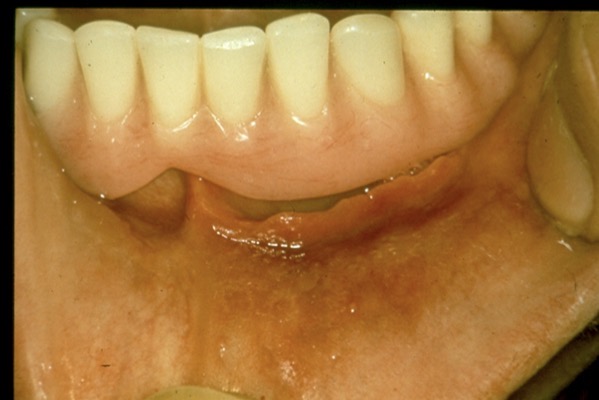

Condition?

Epulis Fissuratum

(a.k.a. denture induced fibrous hyperplasia)